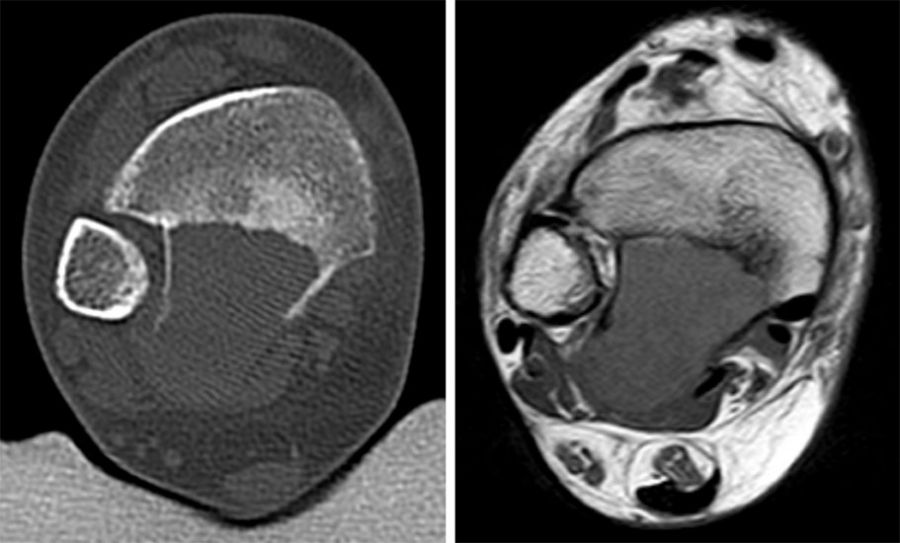

Das solitäre Enchondrom ist von Enchondromatosen, also disseminierten Enchondromen der Extremitäten und des Achsskeletts, abzugrenzen. Die Entartungswahrscheinlichkeit ist für Enchondromatosen wie dem M. Ollier (Abb. 18a und b) oder dem Maffuci-Syndrom deutlich erhöht und wird in der Literatur bis zu 25% angegeben. Klinische und radiologische Hinwiese für eine Entartung beinhalten Kortikalisveränderungen, wie -verdickung, -destruktion und die enossale Kortikalisarrosion, welche in der CT-Bildgebung mehr als 2/3 der Zirkumferenz des betroffenen (Röhren-) Knochens umfasst.

Das primäre, konventionelle Chondrosarkom des Fußes, welches nicht sekundär aus einem Enchondrom oder einer Exostose (exophytäres bzw. exostotisches Chondroarkom) sondern de novo entsteht, zeigt, ähnlich wie das Enchondrom, eine Prädilektion für die kurzen Röhren­knochen (Abb. 19). Das durchschnittliche Alter liegt hier bei 52 Jahren mit einer Bevorzugung des männlichen Geschlechts. In Abhängigkeit der Lokalisation und Graduierung des Tumors umfasst die geeignete operative Therapie die intraläsionale Curettage (G1) bis hin zur Amputation (G3) 34. Das Chondrosarkom ist nicht Strahlen- oder Chemotherapie-sensibel. Eine vollständige chirurgische Resektion bleibt deshalb die einzig sinnvolle Therapiemöglichkeit.